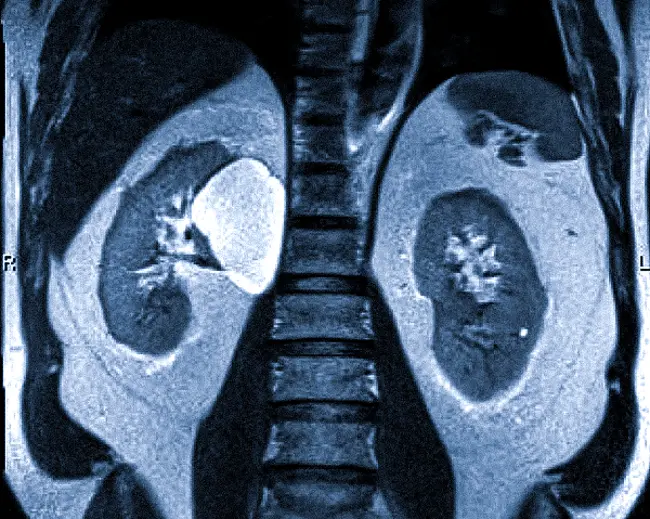

Что показывает МРТ почек? Этот метод хорошо визуализирует мягкие ткани, паренхиму, нервы, сосуды, а также подкожно-жировую и висцеральную клетчатку. При использовании контрастного вещества исследование кровеносной системы проходит гораздо более детально. Результаты сканирования позволяют выявить следующие патологии:

- опухоли почек;

- кистозные образования;

- деформации в почках и мочеточниках;

- туберкулез;

- гидронефроз;

- пиелонефрит;

- плохое кровоснабжение почек (инфаркт);

- гематомы;

- опущение почек;

- нефролитиаз;

- паразитарные повреждения.

МРТ с контрастированием может точно определить размеры и границы опухолей, оценить сосуды и кровообращение. Если целью исследования являются камни в почках, более эффективным будет использование компьютерной томографии.

На снимках четко просматриваются мочевой и желчный пузырь, надпочечники. Магнитно-резонансная томография помогает выявить патологические изменения в забрюшинном пространстве и оценить состояние соседних мягких тканей и сосудов.

На МР-томограммах в аксиальной проекции органы имеют нормальную форму и положение. Структура изображений неоднородная, что обусловлено наличием в субкапсулярных отделах нижней трети левой почки простой кисты размером 4 мм, заполненной серозным содержимым. В передних отделах нижней трети правой почки отмечается объемное образование округлой формы с четкими контурами, интенсивно накапливающее контрастное вещество в позднюю артериальную фазу сканирования, что создает яркий МР-сигнал.

На снимке МРТ видно наличие кисты почки.